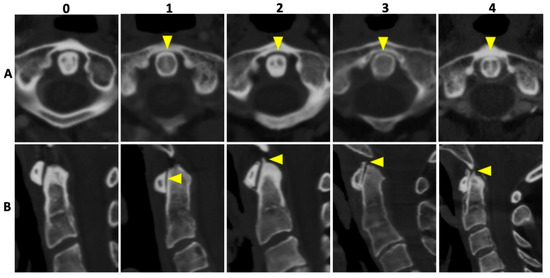

2.4. Image Reading